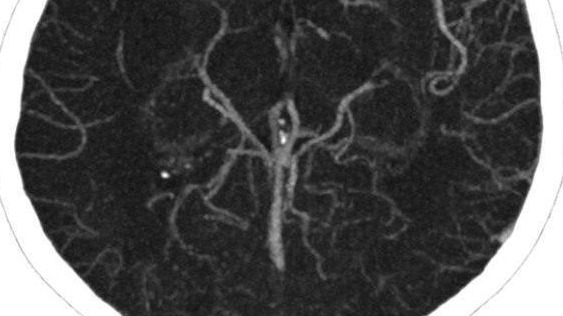

Фото: Telegram / Московская медицина

Московские хирурги спасли молодую женщину от инсульта, удалив огромный тромб из мозговой артерии. Об этом сообщил руководитель регионального сосудистого центра Владимир Кузнецов.

К врачам обратилась 25-летняя девушка с жалобами на головокружение, слабость и онемение конечностей. У нее был диагностирован ишемический инсульт.

— Из артерии удалось извлечь червеобразный сгусток длиной 25 сантиметров. Изначально мы даже заподозрили, что в сосуде мозга женщины поселился паразит. Но исследования показали, что это все-таки тромб, — рассказал специалист.

По его словам, после операции пациентка прошла углубленное обследование, которое выявило, что у нее развилось опасное аутоиммунное заболевание — антифосфолипидный синдром. При этой болезни риск образования тромбов увеличивается в разы, следует из сообщения в Telegram-канале.